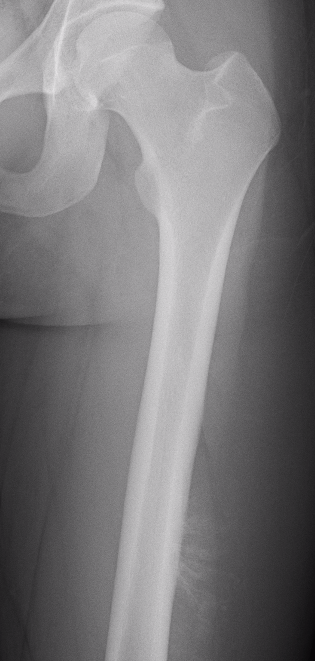

Xray

Often diaphyseal

- diffuse permeative destruction

- can be subtle

Periosteal reaction

- Codman's triangle / onion skinning / sunburst appearance

Ewing's acomion Ewings lesser trochanter

Ewing proximal femur

Ewing's femoral diaphysis, subtle on xray with large soft tissue component